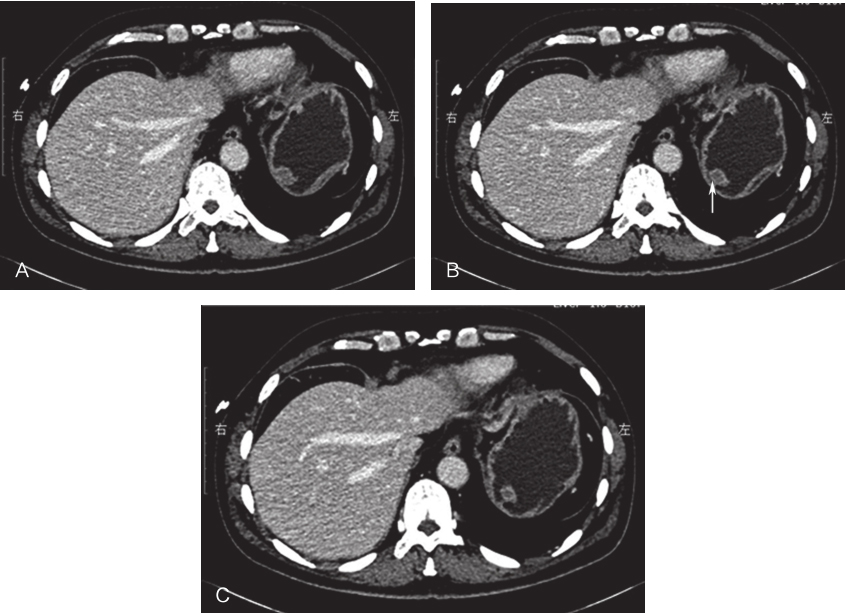

1小时条评论胃肠间质瘤(gastrointestinalnbsp;stromalnbsp;tumor,GIST)作为消化系统中较常见的软组织来源肿瘤,其伴发其他恶性肿瘤的概率并不低,根据美国得克萨斯大学MD安德森肿瘤中心(Thenbsp;Universitynbsp;ofnbsp;T...